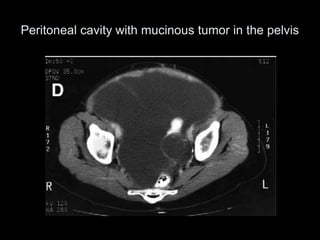

Peritoneal cavity with mucinous tumor in the pelvis

Peritoneal cavity withmucinous tumor in the pelvis